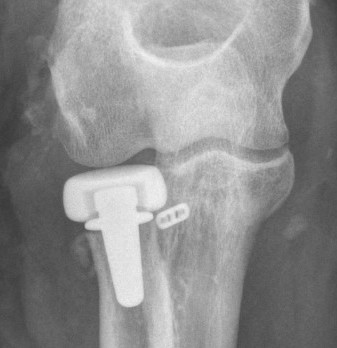

![]() |

Overstuffing

| Lesser sigmoid notch | Symmetry of ulnohumeral joint |

|---|---|

|

Radial head shoulder articulate with lesser notch

Ensure no gapping of lateral ulnohumeral joint |

- cadaveric study

- increased medial ulno-humeral joint line gapping with overlengthening of 6 or 8 mm

- increased lateral ulno-humeral joint line gapping with overlengthening of 2 mm